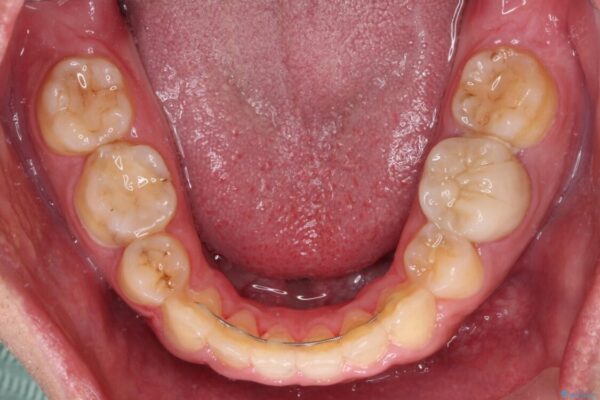

治療前

• 後戻りでデコボコの前歯 インビザライン矯正治療 治療前画像